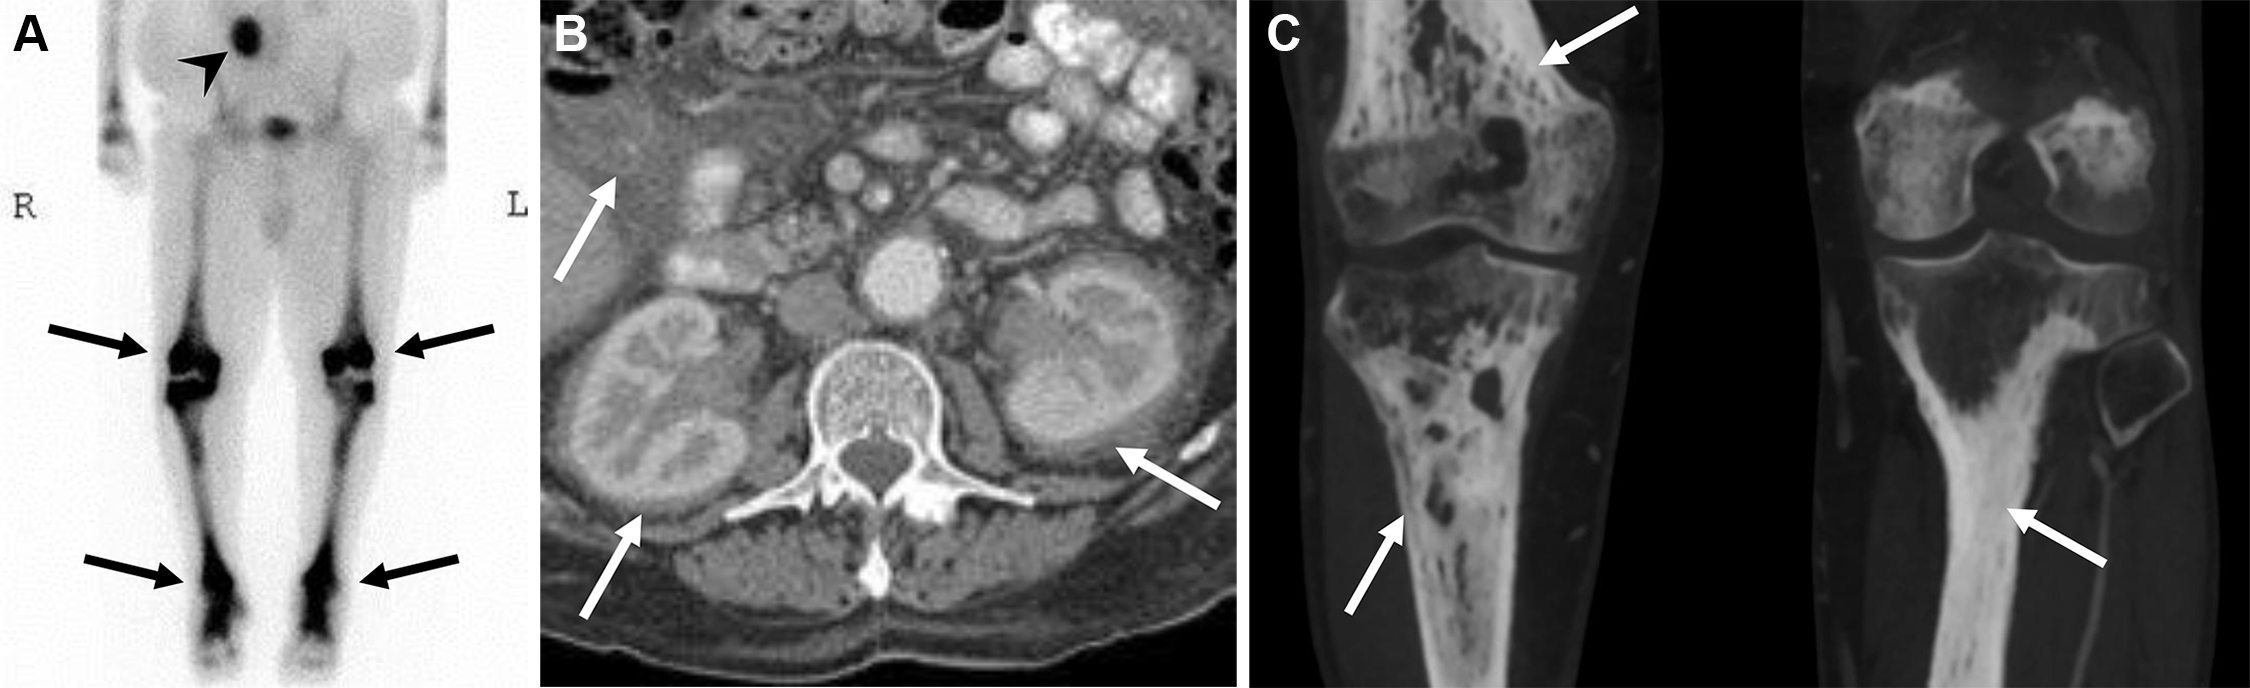

Uomo di 35 anni con lombalgia in peggioramento da 6 mesi e recente insorgenza di dolore alla spalla sinistra, associati a inappetenza e malessere. È stata eseguita una scintigrafia ossea trifasica con 99mTc-MDP.

La fase di flusso ha mostrato un’ipervascolarizzazione a livello delle vertebre L3-L4 (a). Le immagini statiche di blood-pool (b. 1) e tardive (b. 2) della regione lombare hanno evidenziato un aumentato accumulo ematico e una captazione tardiva del tracciante nella medesima regione a livello L3-L4. L’immagine whole-body di blood-pool (c) e le immagini tardive (d) acquisite dopo 3 ore hanno mostrato un’aumentata captazione a livello delle vertebre L3-L4, dell’articolazione sterno-claveare sinistra e del manubrio dello sterno. Le immagini SPECT-TC della vertebra L4 (e) hanno rivelato una lesione distruttiva con interessamento dei tessuti molli pre- e paravertebrali; reperti simili di distruzione e raccolta fluida sono stati notati nell’articolazione sterno-claveare sinistra (f). Nella lesione vertebrale si osserva un sequestro a bottone (freccia nera). La RM eseguita 2 giorni dopo ha confermato una spondilodiscite.